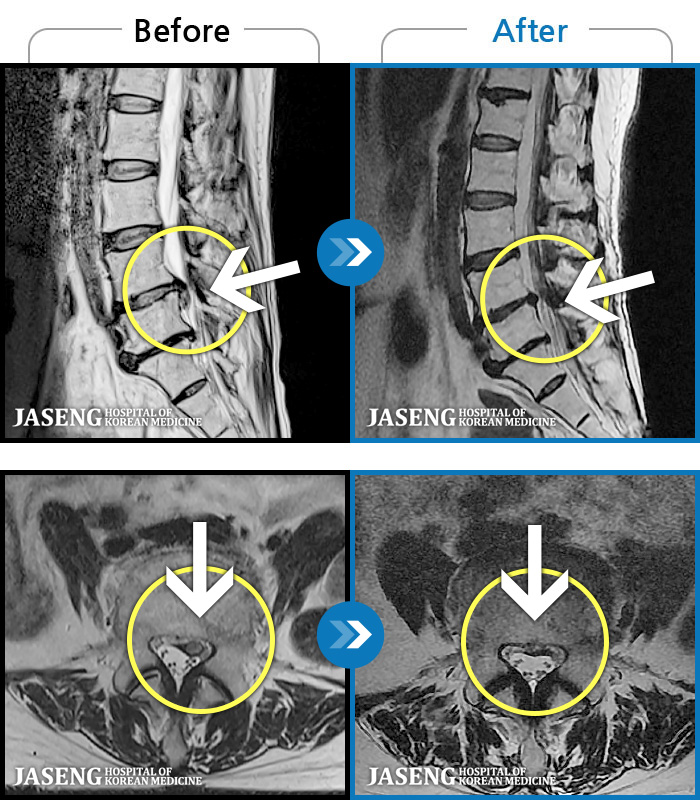

- MRI ġ

MRI ġ

1,237 MRI ũ ʸ Ȯϼ.